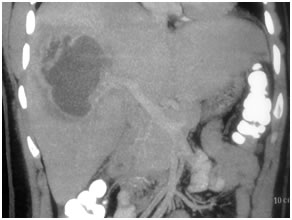

HCC in a non cirrhotic liver

Large HCC in seg 2 & 3

Large HCC in seg 2&3